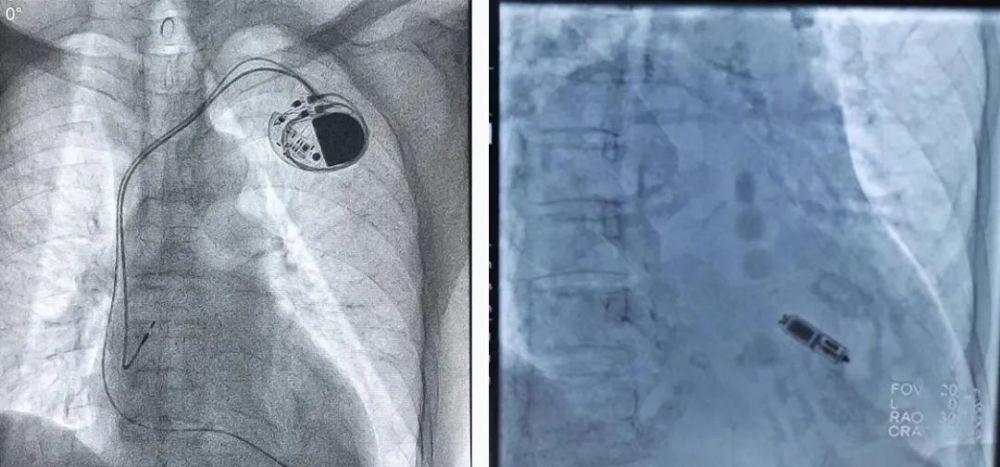

心脏起搏器伤口图片,心脏起搏器手术过程

新蔡同安医院首例永久性人工心脏起搏器植入术成功开展!

厉害了!中医院心内科成功开展首例永久性心脏起搏器植入手术

起搏器被放入心脏过程详解!

仅重2克!桂医二附院成功完成首例无导线起搏器植入手术!

心脏起搏器手术过程

心脏起搏器术后图片

心脏起搏器手术图片

心脏起搏器图片

安装心脏起搏器图片